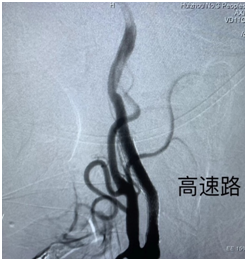

術(shù)中造影顯示:右側(cè)頸內(nèi)動脈狹窄,狹窄率95%。醫(yī)生在陳阿姨的頸動脈中應用球囊擴張植入支架的方法,打通了患者狹窄的血管,避免了腦卒中的發(fā)生。該介入術(shù)創(chuàng)傷小、操作簡單、起效快、恢復快,是目前較為先進的治療方式。